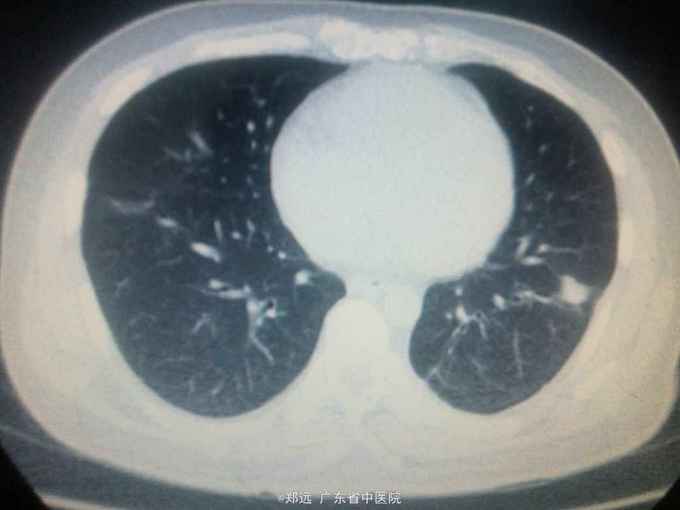

体查:双下肺湿啰音。三尖瓣区3/6级收缩期杂音。 胸部ct:双肺斑片结节影并空洞形成,左胸少量积液。血色素88克/升,白细胞11.48,中性粒81.3%,降钙素原14.84,ALT 121,AST 134.超声提示三尖瓣赘生物,三尖瓣大量返流。血培养金葡菌。

诊断:急性感染性心内膜炎,脓毒症,肺脓肿,丙型肝炎。 治疗:入院予万古霉素0.5克q6h,经治疗五日血象正常,降钙素原1.54,但仍反复高热,考虑肺脓肿合并阴性菌感染,加用头孢哌酮舒巴坦3克q12h,治疗五日仍有发热,血培养阴性,白细胞正常,降钙素原0.15,头孢哌酮舒巴坦改为美罗培南0.5克q8h,两日后无再发热,维持该方案至治疗四周后改予万古霉素0.5克q8h加美罗培南0.5克q12h继续治疗两周,复查超声提示三尖瓣熬生物较入院时缩小约三分之一,多次血培养阴性,胸部ct提示肺部炎症明显吸收予出院。出院后患者仍间发热,出院后约七周再次返院,查白细胞13.88,中性粒65.9%,血色素正常,降钙素原0.55,血培养提示溶血葡萄球菌,胸部ct示双肺多发感染灶,较前吸收,胸腔积液已吸收。予原万古霉素加美罗培南方案治疗,两日后无发热,治疗三周后多次血培养阴性,胸部ct提示肺部感染基本吸收,行三尖瓣赘生物切除并三尖瓣修补术,术中见三尖瓣后瓣瓣叶破坏严重,赘生物大小约2*1厘米。术后恢复良好,维持万古霉素加美罗培南治疗一周后改予万古霉素0.5克q8h加阿米卡星0.4克q12h治疗两周,赘生物及多次血培养阴性予出院。